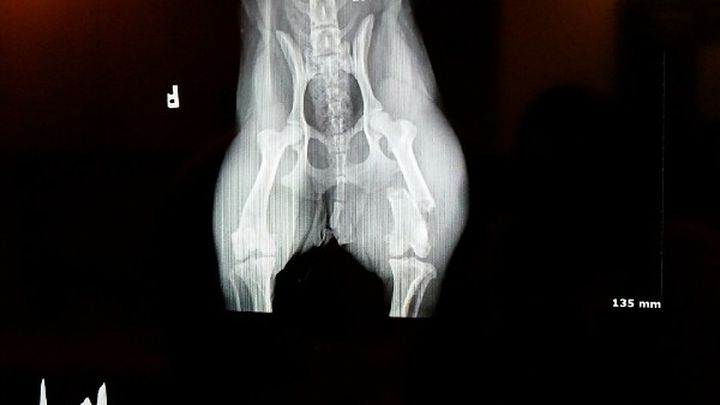

My sweet little girl Sadie escaped out of our backyard earlier this morning. Unfortunately, someone picked her up and made the decision to toss her small body off of a freeway overpass. Somehow, she survived with only a broken leg but the fracture is bad enough that it will require surgery. My sweet girl is only a little over a year old and has a lot of life left to live. The surgery is simple and the vet assures us she will make a full recovery.

The surgery itself is going to cost three thousands dollars. This covers the xrays, the pain medication, the surgery, and all of the follow ups. We just don't have the kind of funds required to pay for her surgery. Without this surgery, I would have to put my Sadie to sleep. It breaks my heart to think of that possibility and I'm asking for anyone who could help us out at all. Anything would be appreciated. We don't have a lot of time to try and raise the money for her surgery. If you could share this story and pass it along we would be truly blessed.